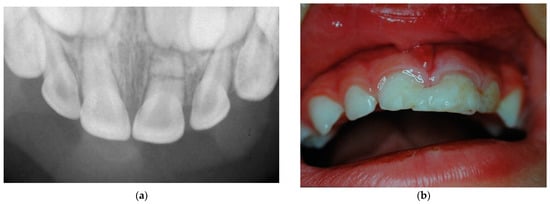

- Di Giorgio, G.; Zumbo, G.; Saccucci, M.; Luzzi, V.; Ierardo, G.; Biagi, R.; Bossù, M. Root Fracture and Extrusive Luxation in Primary Teeth and Their Management: A Case Report. Dent. J. 2021, 9, 107. [Google Scholar] [CrossRef] [PubMed]